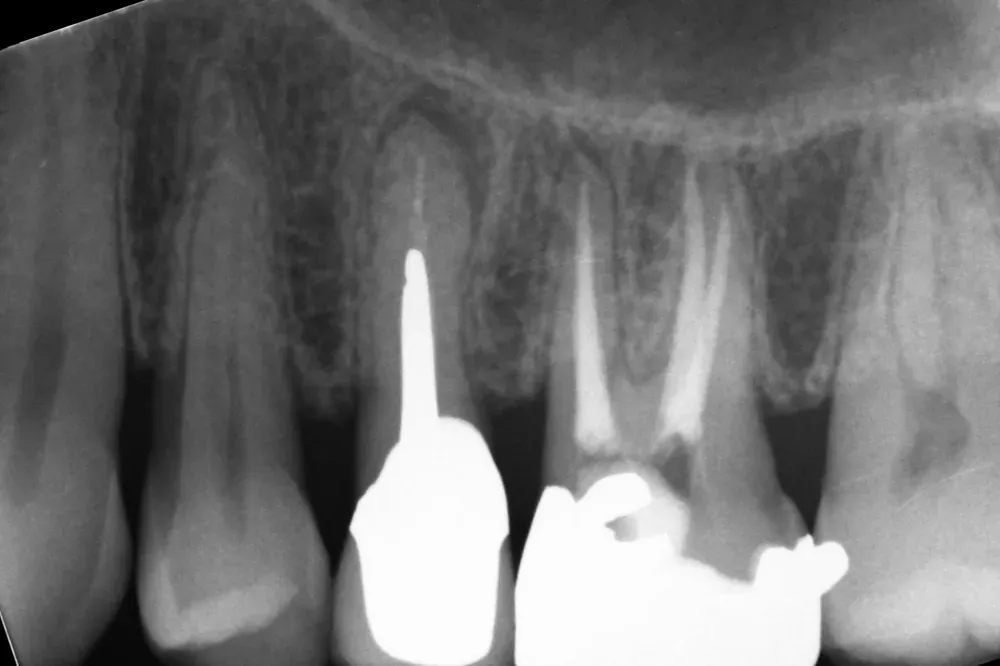

Le immagini radiografiche che seguono testimoniano alcune delle tante soluzioni tecniche che ho utilizzato per le arcate a carico immediato nel corso della mia carriera. Ogni caso presenta sfide diverse e richiede un approccio personalizzato.

Impianto in Titanio di forma evoluta (Newton - Kalodon)